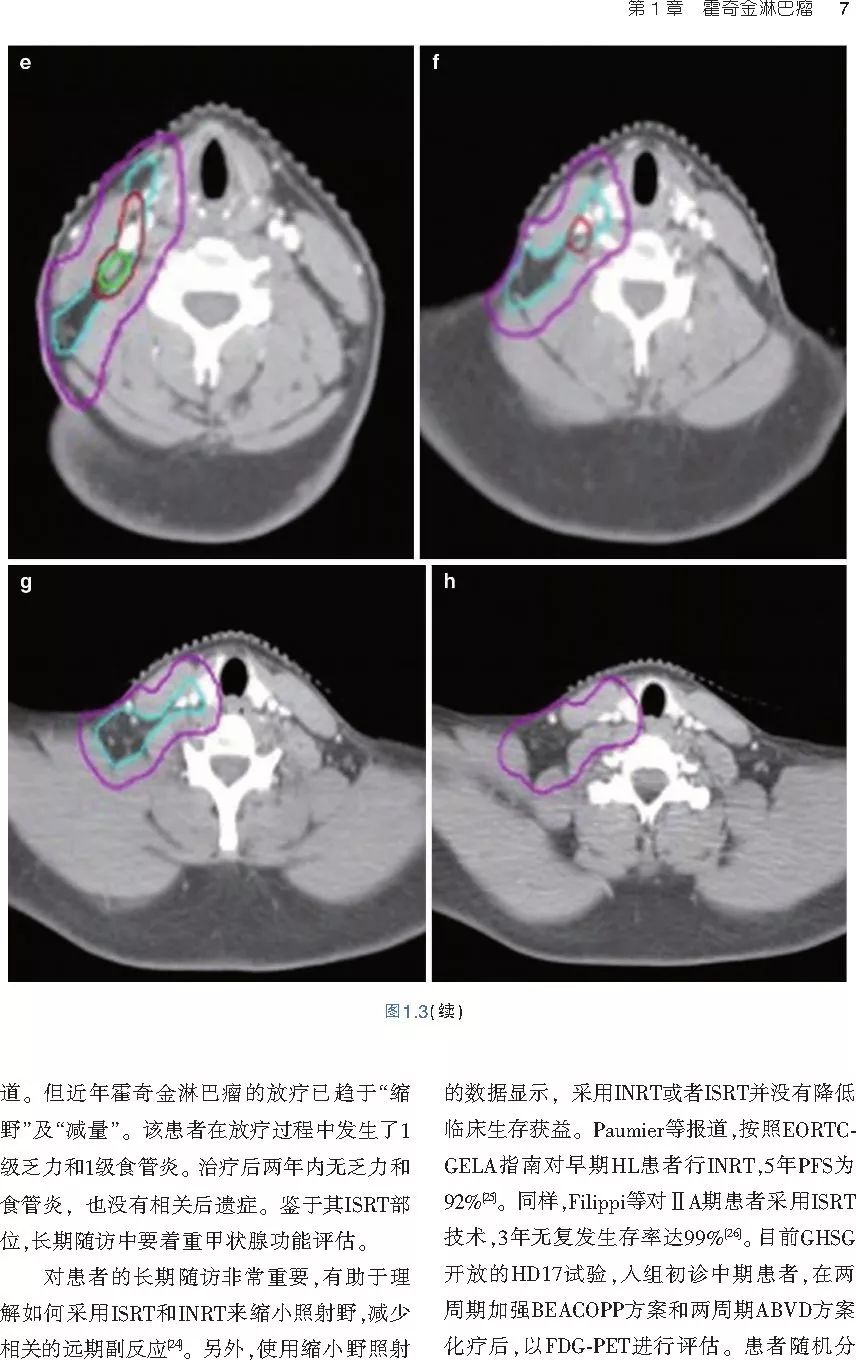

❤ 展开疾病诊断、病理描述及治疗方向的详细阐述,包含医学影像,图文并茂,深入浅出。

本书旨在帮助临床医生对常见血液系统恶性肿瘤疑难病例进行管理,包括霍奇金淋巴瘤、非霍奇金淋巴瘤和白血病患者,并通过多个病例进行阐述。案例讨论遵循标准格式,包括临床描述,其次是与诊断相关的病理描述和分期,然后详细讨论治疗选择。最后,确定治疗方案,并提供所使用的规划放疗技术/方式的图像。对放射肿瘤医生进行临床决策非常有帮助,对于血液病临床医生也有很好的指导作用。